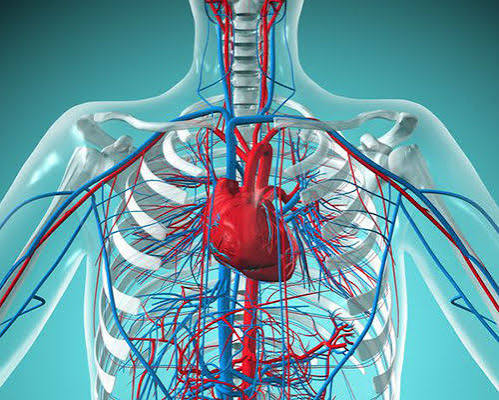

پیام مازند - آخرین خبر / در این ویدئو از برنامه صبحانه ایرانی دکتر مسعود قاسمی، متخصص قلب و عروق درباره این موضوع توضیح میدهد.

پیام مازند - آخرین خبر / در این ویدئو از برنامه صبحانه ایرانی دکتر مسعود قاسمی، متخصص قلب و عروق درباره این موضوع توضیح میدهد.